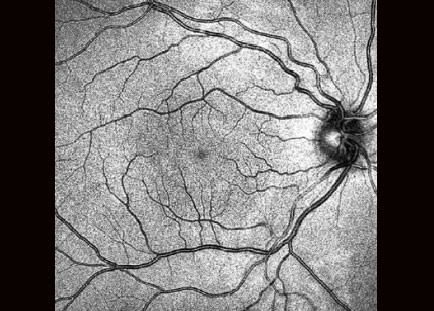

Завдяки визнаній оптиці Canon, Xephilio OCT-A1 пропонує чудову якість зображення. З цифровою розподільчою здатністю до 1.6 мкм система дозволяє чудово диференціювати структури та окремі шари сітківки.

Зображення високої якості

Xephilio OCT-A пропонує відмінну оптичну розподільну здатність. Усередненням безлічі сканів (до 200)досягається прекрасна якість зображення з дивовижною деталізацією.

Висока чіткість, збільшена глибина, широке поле зору

За допомогою Xephilio OCT-A1 ви можете усереднити до 200 сканувань, щоб досягти розподільчої здатності зображення, що дозволяє детально бачити як структуру шарів сітківки, так і пошарову структуру скловидного тіла. Для оптимальної візуалізації система пропонує спеціальні режими сканування для скловидного та судинного зображення, а також особливо широку ширину сканування до 13 мм

Надійне розпізнавання 10 шарів

Xephilio OCT-A1 компанії Canon може автоматично виявити та розрізнити 10 шарів сітківки, включаючи мембрану Бруха (BM) - завдяки чудовій якості зображення та розподільчій здатності.

НЕЙМОВІРНА ДЕТАЛІЗАЦІЯ